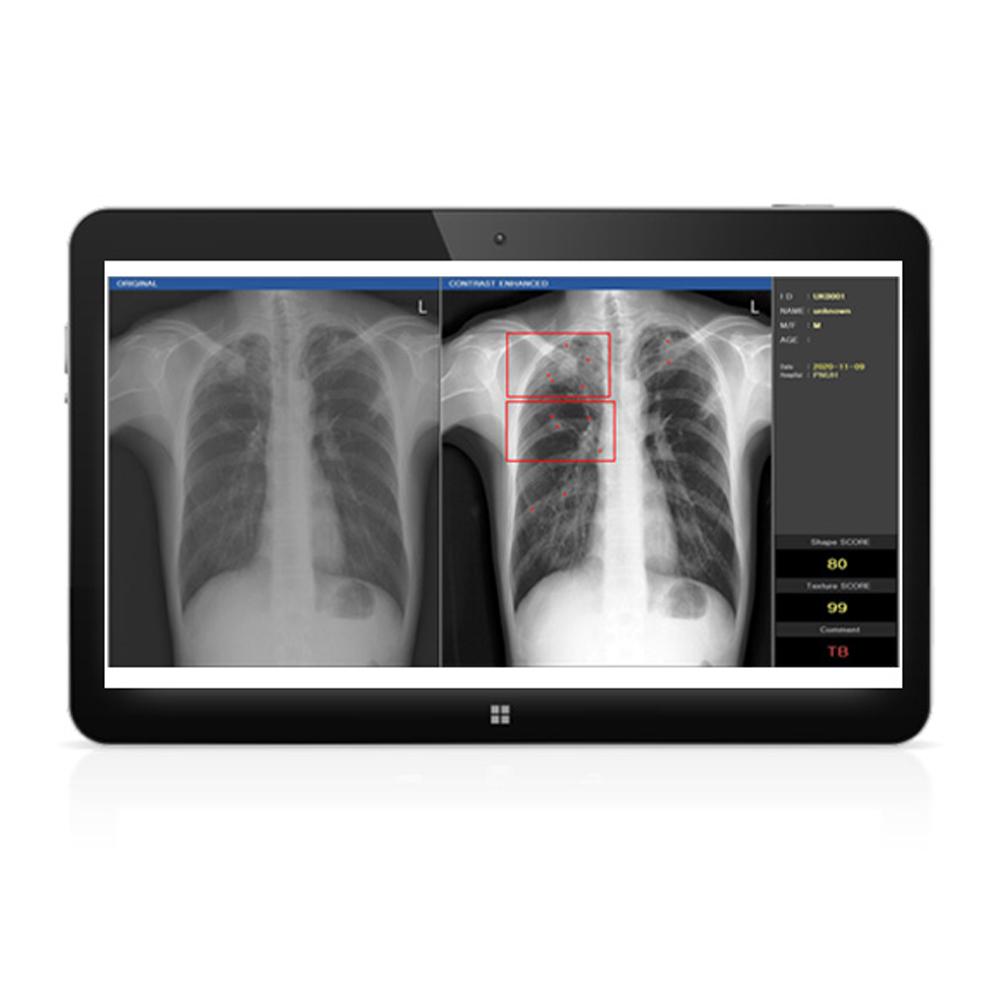

DxRAD(Digital X-ray Radiography Auto Decipher based on AI)

The DxRAD is a complementary tool that fits easily on a regular chest X-Ray scan to detect three kinds of chest diseases instantly; normal, abnormal and tuberculosis allowing patients to receive their results and start treatment immediately to avoid further transmission and infections. DxRAD running process is that after scanning chest, the first signal reaches the DxRAD and the result goes to the server of the hospital. From the transferred file, we can see the results. Also the result can be stored in the second hard disk to be used for deep learning and improve future readings..

The DxRAD is a complementary tool that fits easily on a regular chest X-Ray scan to detect three kinds of chest diseases instantly; normal, abnormal and tuberculosis allowing patients to receive their results and start treatment immediately to avoid further transmission and infections. DxRAD running process is that after scanning chest, the first signal reaches the DxRAD and the result goes to the server of the hospital. From the transferred file, we can see the results. Also the result can be stored in the second hard disk to be used for deep learning and improve future readings..

Auto decipher normal, abnormal, tuberculosis

DxRAD Development

Need for exact examination of tuberculous (Chest X-Ray)

70% of hospitals do not have any Radionic Technologist

Patients have not received exact tuberculous test through chest X-Ray

For tuberculous, the early diagnosis is key

DxRAD Development

Need for exact examination of tuberculous (Chest X-Ray)

70% of hospitals do not have any Radionic Technologist

Patients have not received exact tuberculous test through chest X-Ray

For tuberculous, the early diagnosis is key